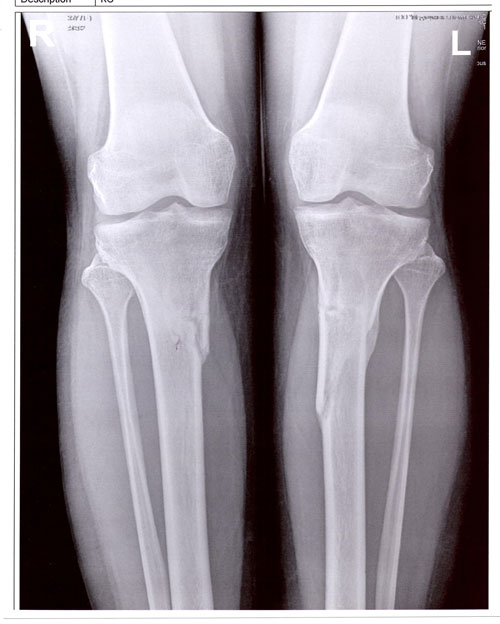

рентген в 60 дней.

Сращение идёт хорошо. Делаем рентген в 90 дней и готовимся к снятию.